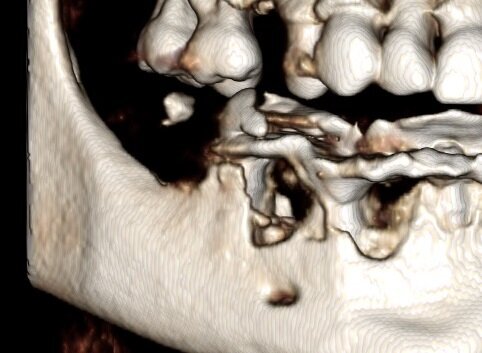

Dn. 18.09.2013 r. w znieczuleniu przewodowym zostały usunięte wszystkie zęby. Celem dokładnego usunięcia ziarniny przed ekstrakcją wykonano ucięcie wg Widmanna (Ryc. 3). Jednym z warunków powodzenia zabiegu jest dokładne usunięcie zmienionych chorobowo tkanek miękkich tak, by pozostawić zdrowe.

Implanty zostały wprowadzone wg zasady przylegania w cieniu, tzn. wszczep musi na całej swojej długości mieć kontakt z którąś ze ścian zębodołu 1-2 mm subkrestalnie (Ryc. 4). W przypadku konieczności użycia membrany, musi ona mieć możliwość rozpostarcia się nad ubytkiem kostnym i implantem tak, aby odległość pomiędzy membraną a wszczepem nie była mniejsza niż 2 m (Ryc. 3). Wszczepy o